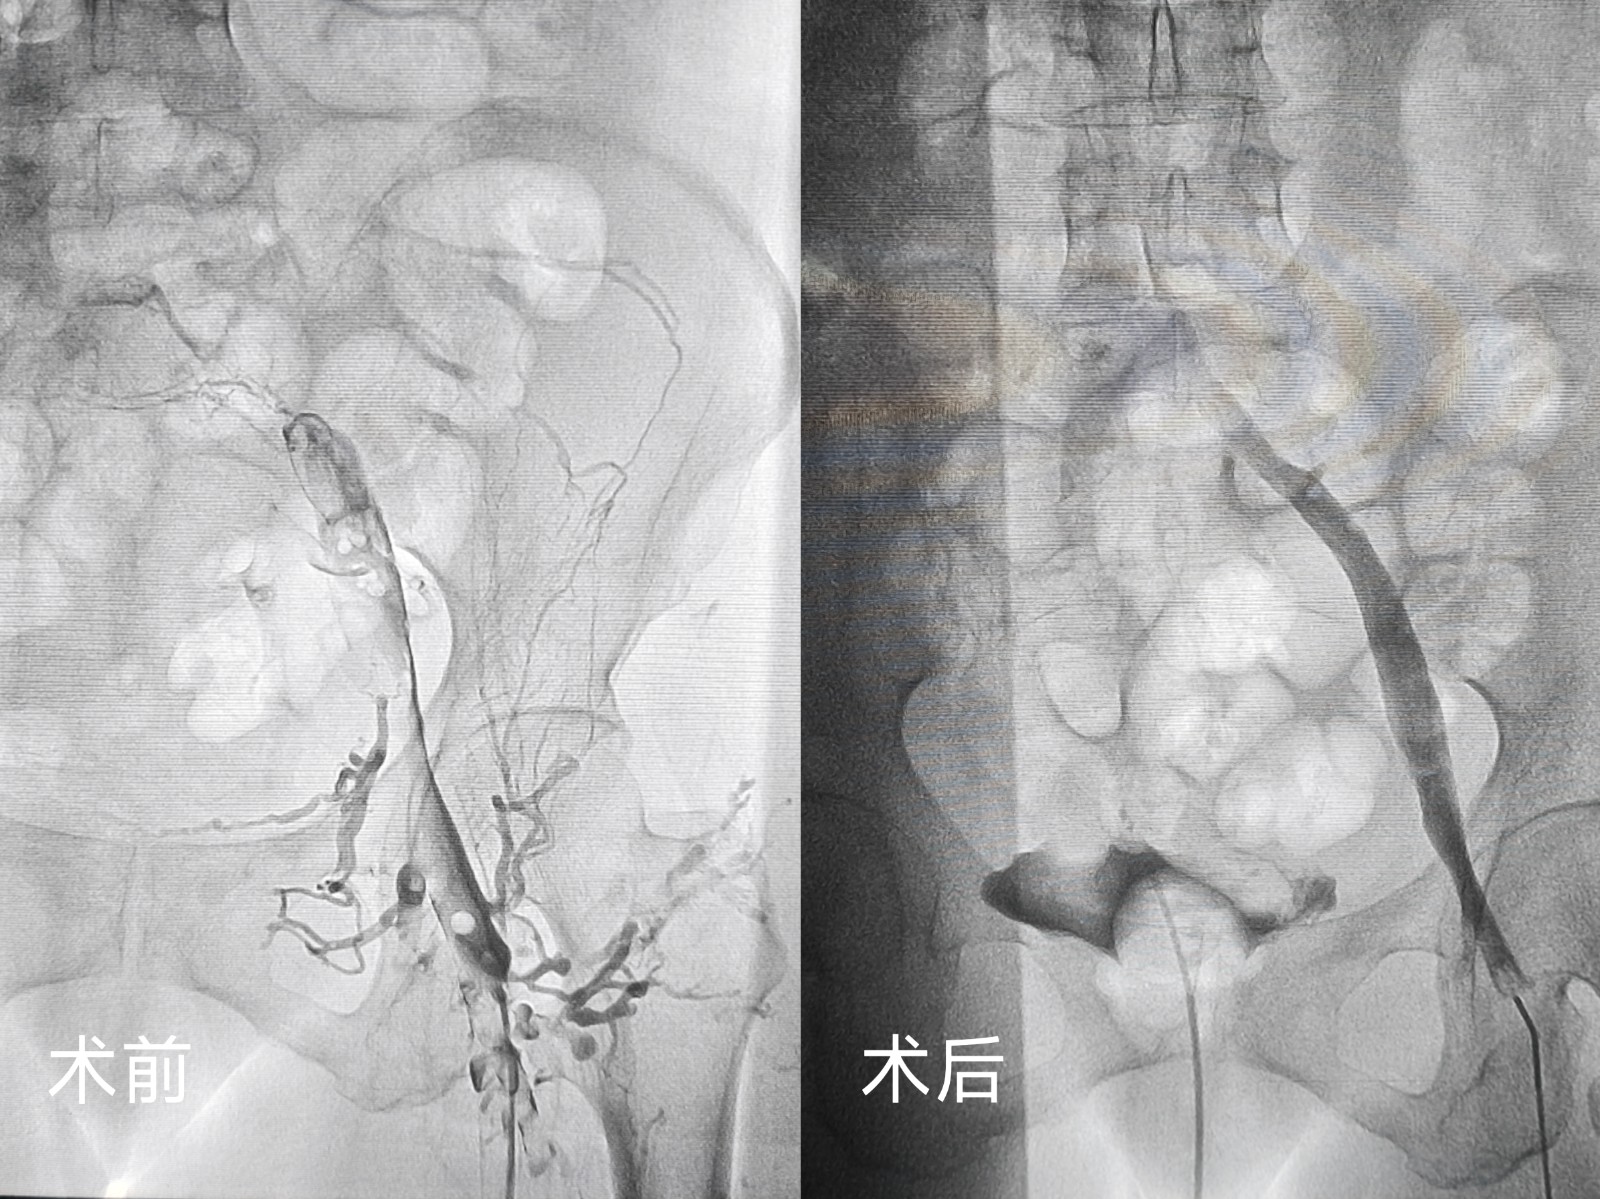

鄂西北首例应用患者因外伤导致双下肢深静脉血栓,转入十堰市人民医院心胸大血管外科时已在外院接受滤器置入术。患者外伤术后同时合并贫血,病情复杂且风险较高。传统的治疗方案失血量较高,科室医疗团队结合患者具体情况,制定了个性化治疗方案,决定采用外周静脉取栓支架系统实施下腔静脉及下肢静脉取栓术。手术过程中,团队发现此前置入的滤器内已形成血栓,为避免血栓脱落风险,当即调整手术方案,在精准置入新滤器后,成功回收旧滤器,同时利用外周静脉取栓支架系统高效清除静脉内阻塞血栓。

术后,患者双下肢肿胀症状得到显著改善,肢体活动逐渐恢复,贫血状况也在针对性治疗下稳步好转。